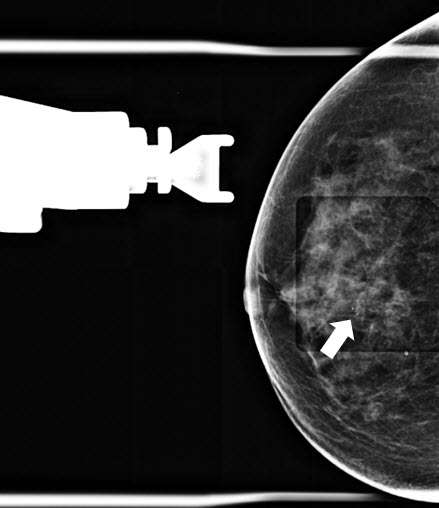

- Radiologist confirms appropriate compression of breast tissue, appropriate visualization of biopsy target, and performs adjustments if necessary (Figure 1).

Figure 1. Craniocaudal (CC) tomosynthesis scout image of the right breast shows coarse heterogeneous calcifications measuring 5 mm with grouped distribution at 12 o’clock at middle depth located 4 centimeters from the nipple (arrow).